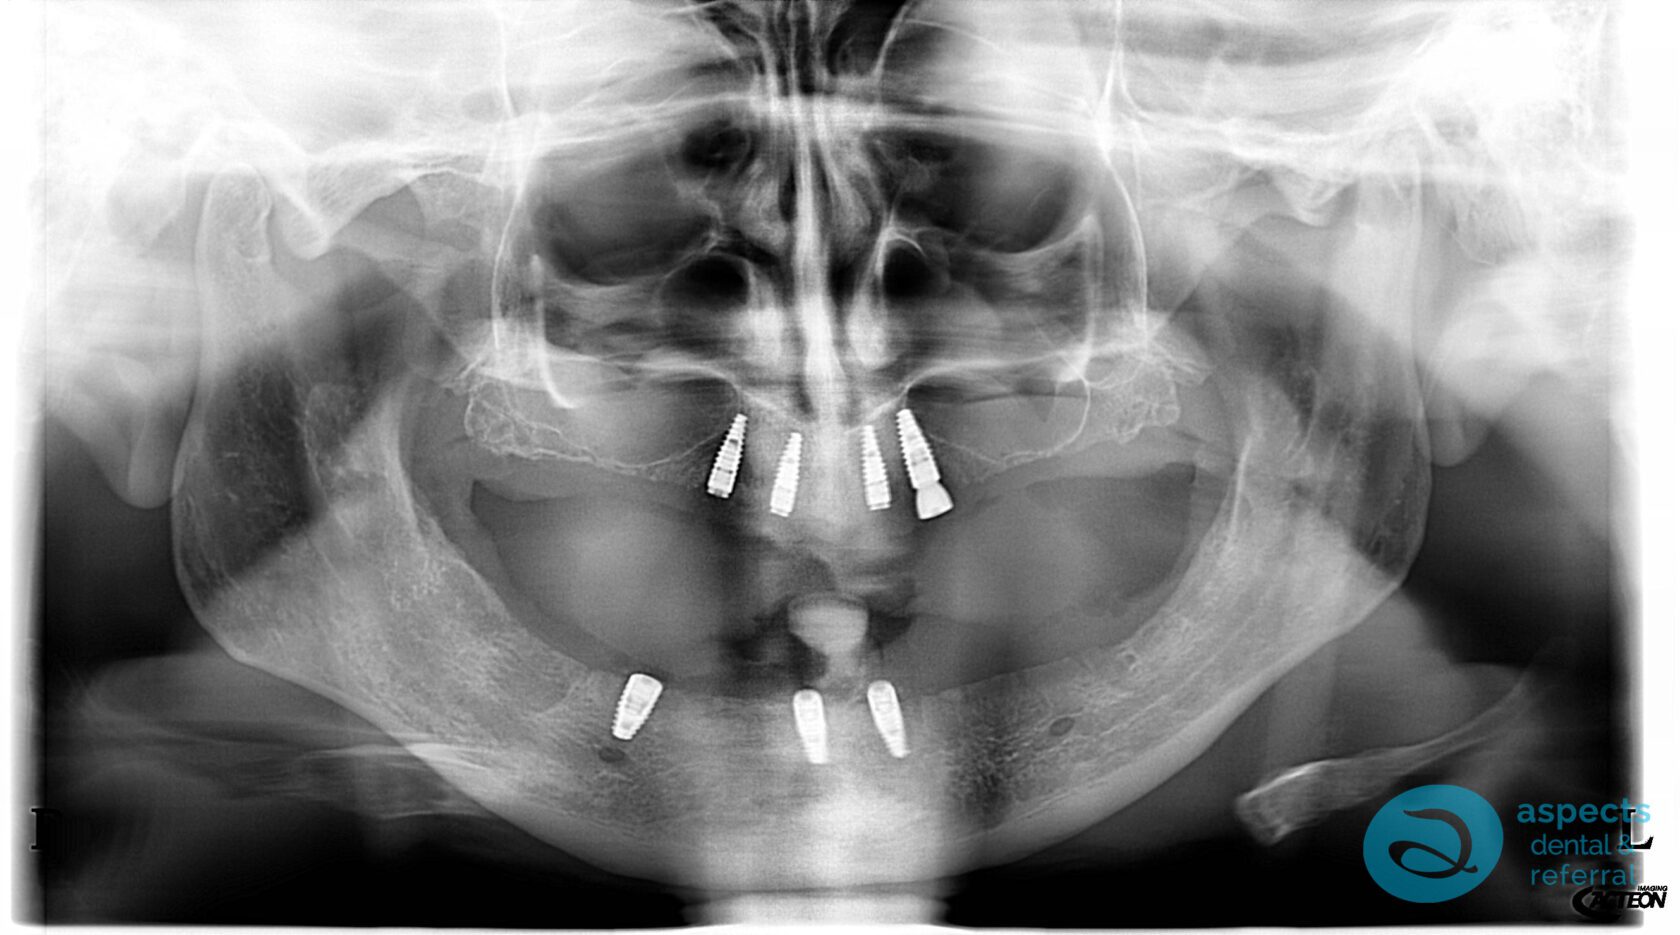

Following an appropriate healing period to allow for soft tissue and bone stabilization, Dental Implants were placed in both the maxilla and mandible. After successful osseointegration, implant-retained overdentures were fabricated and delivered, significantly improving prosthetic stability, function, and patient satisfaction.

After Implant-Retained Overdentures Xray